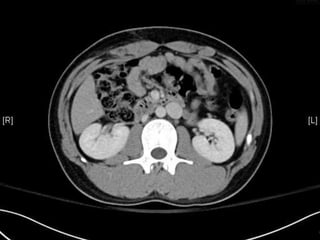

• CT:

 Shanmuganathan(2004)

 Sen:97%, spe:98%, accuracy:98% in penetrating stab wds

 Velmahos(2005)

 GSW: Sen 90.5, Spe: 96%

Radiology 2004:231:775-784

J trauma 2005:59:1155-1161